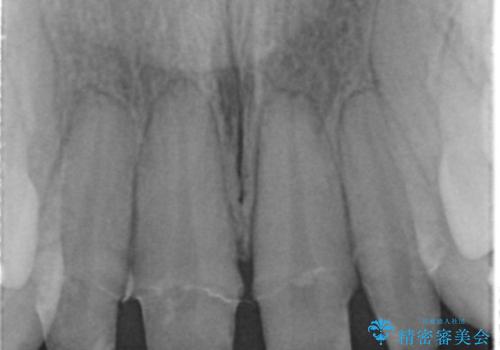

- 仮歯のまま放置してしまい、変色を改善しきれいなセラミッククラウンをいれたい、と希望され来院されました。

特に虫歯の再発や神経の症状等問題を認めなかったので、審美的に優れるセラミッククラウンに仮歯を置き換えていきます。